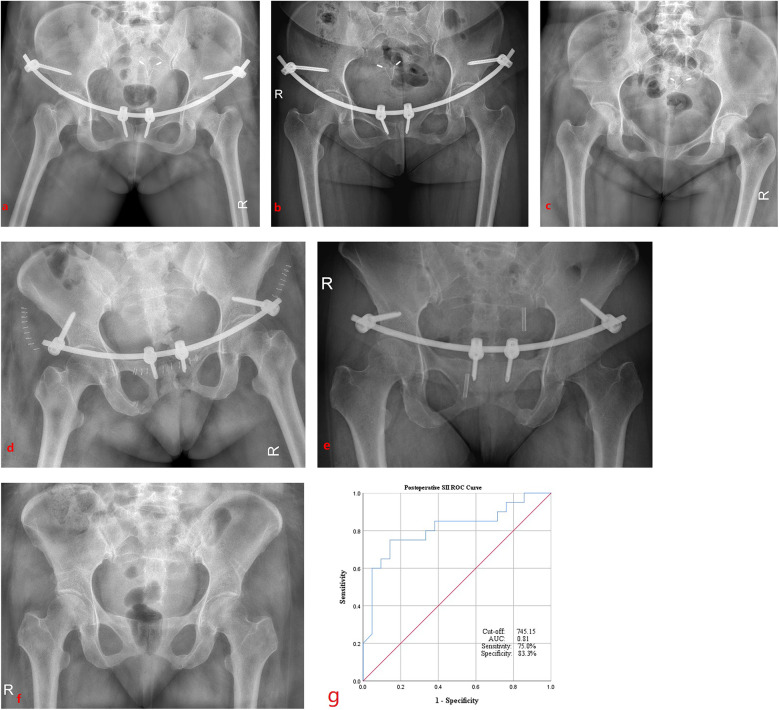

Results: A total of 41 patients were included in the study. No significant differences in gender or age were observed between the robot-assisted and non-robot-assisted groups. Compared to the non-robot-assisted group, the robot-assisted group demonstrated significantly shorter operative duration, reduced intraoperative bleeding, and a lower incidence of LFCN palsy (P < 0.05). In addition, the postoperative SII was significantly lower in the robot-assisted group (P < 0.05). ROC curve analysis revealed that postoperative SII exhibited a predictive capability for surgical invasiveness, with an optimal cut-off value of 745.15 (area under the curve = 0.81; sensitivity, 75%; specificity, 83.3%).

Conclusion: The findings suggest that the postoperative SII may serve as a valuable biomarker reflecting the degree of surgical invasiveness associated with robot-assisted or conventional INFIX procedures for anterior pelvic ring fractures. A postoperative SII value exceeding 745.15 demonstrates promising predictive utility for elevated surgical trauma, with a specificity of 83.3% and sensitivity of 75%.